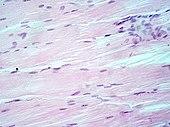

H&E is the combination of two histological stains: hematoxylin and eosin. The hematoxylin stains cell nuclei blue, and eosin stains the extracellular matrix and cytoplasm pink, with other structures taking on different shades, hues, and combinations of these colors.[5][6] The stain shows the general layout and distribution of cells and provides a general overview of a tissue sample's structure.[7] Hence a pathologist can easily differentiate between the nuclear and cytoplasmic parts of a cell.

Hematoxylin principally colors the nuclei of cells blue or dark-purple,[6][15][14] along with a few other tissues, such as keratohyalin granules and calcified material. Eosin stains the cytoplasm and some other structures including extracellular matrix such as collagen[5][7][14] in up to five shades of pink.[8] The eosinophilic (substances that are stained by eosin)[5] structures are generally composed of intracellular or extracellular proteins. The Lewy bodies and Mallory bodies are examples of eosinophilic structures. Most of the cytoplasm is eosinophilic and is rendered pink.[10][15] Red blood cells are stained intensely red.